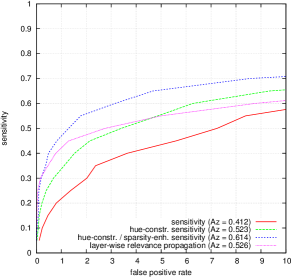

Artifacts from various visualization algorithms are illustrated in Fig. 4. First, it can be seen that the original sensitivity criterion is inadequate to finely detect lesions. Sensitivity maps seem to indicate that if lesions grew in size, the diagnosis would be consolidated. The hue constraint prevents the lesion detections from growing. Second, it can be seen that, due to the drafting effect, blood vessels (lesion confounders) in the vicinity of lesions are detected, both in the hue-constrained sensitivity maps and in the layer-wise relevance propagation maps. The resulting false detections are not necessarily connected to the true detection, so they cannot be removed easily through image post-processing techniques: they have to be removed beforehand, hence the proposed approach.

FROC curves are reported in Fig. 6 for ‘net B’; areas under the limited FROC curve for all three ConvNets are summarized in Table 3. It appears that the number of false alarms is rather large, particularly in the case of microaneurysm detection. The reason is that human experts primarily segmented the most obvious lesions, while screening algorithms need to focus on the most subtle lesions as well. In other words, many true lesions are counted as false alarms. Of course, this comment also applies to competing automatic solutions. To show the value of our detections, the proposed solution was compared in Fig. 7 to results reported in the literature, following the DiaretDB1 standardized procedure (see section 5.3.2). Most authors reported a single (sensitivity, specificity) pair: this is what we reported in Fig. 7. Some authors reported ROC curves; in that case, we also reported a single (sensitivity, specificity) pair: the one closest to the (sensitivity = 1, specificity = 1) coordinate. Note that all competing solutions (Kauppi et al., 2007; Yang et al., 2013; Franklin and Rajan, 2014; Kumar et al., 2014; Bharali et al., 2015; Mane et al., 2015; Dai et al., 2016) are trained at the lesion level, while ours is trained (in Kaggle-train) at the image level.

Three ConvNets were trained to detect referable DR in the Kaggle-train dataset, using the proposed heatmap optimization procedure. Then, we evaluated how well those ConvNets could detect lesions in the DiaretDB1 dataset, without retraining them. For lesion detection at the image level, they outperformed previous algorithms, which were explicitly trained to detect the target lesions, with pixel-level supervision (see Fig. 7). This superiority was observed for all lesions or groups of lesions, with the exception of ‘red lesions’. Experiments were also performed at the lesion level: for all lesion types, the proposed algorithm was found to outperform recent heatmap generation algorithms (see Table 3). As illustrated in two examples (see Fig. 9 and 10), the produced heatmaps are of very good quality. In particular, the false alarms detected on the vessels, in the vicinity of true lesions in the unoptimized heatmaps ( maps), are strongly reduced with sparsity maximization (, , ). These experiments validate the relevance of image-level supervision for lesion detectors, but stress the need to optimize the heatmaps, as proposed in this paper. Note that detection performance is not affected much by image quality: very good detections are produced in the blurry image obtained with a low-cost, handheld retinograph (see Fig. 10). This is a very important feature, which opens the way to automated mobile screening. However, it can be observed that the ‘AlexNet’ architecture, which achieves moderate DR detection results, also achieves poor detection results at the lesion level, even after heatmap optimization (see Table 3): to ensure good detection performance at the lesion level, the proposed optimization framework should be applied to ConvNet architectures that achieve good image-level performance.